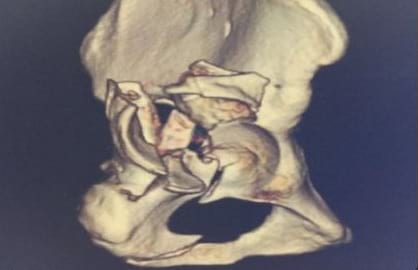

The Trauma Center at Anup Institute of Orthopaedics and Rehabilitation has gained significant expertise in managing complex cases, including pelvi acetabular fractures, calcaneal fractures, spine and hand trauma, among others. The department is well-prepared to handle severely injured patients and regularly trains its staff to provide optimal care.